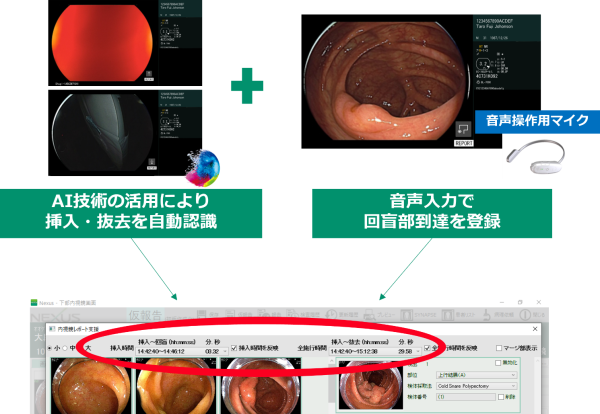

2.検査時間記録機能

AI技術の活用によるスコープの体内挿入・抜去の自動認識と、音声操作による回盲部到達の登録を組み合わせて、JEDに対応した時間記録が可能です。挿入時間、全施行時間をシステム上で計測してレポートに転記することができるため、検査時間の計測漏れを防ぐと同時に、入力の手間を軽減する。

AI技術の活用によって認識されたスコープの体内挿入・抜去時間と、音声操作で登録した回盲部到達時間が記録され、JEDに必要な挿入時間、全施行時間の計測を行う。計測結果に問題がないことを確認し、確定ボタンを押下すると患者付帯情報欄の該当項目に結果が反映される。